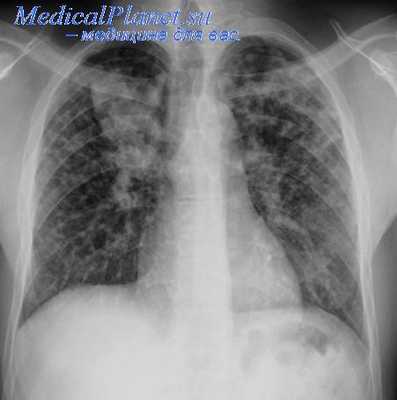

Коллапсотерапия (лат. collapsus ослабевший, упавший + греч. therapeia лечение) — методы лечения туберкулеза путем достижения временного или постоянного спадения (уменьшения объема) пораженного легкого.

Лечебный эффект Коллапсотерапии заключается в том, что наступает рассасывание воспалительных туберкулезных инфильтратов и заживление каверны. Наиболее распространенными теориями механизма действия К. являются: функциональный покой пораженного легкого, лимфатический стаз, венозный застой в спавшемся легком, перегибы мелких бронхов, нейротрофические изменения в спавшейся легочной ткани. Один из этих факторов или все вместе стимулируют репаративные процессы в пораженном легком, приводящие в большом проценте случаев к излечению от активного туберкулеза легких.

Достигнуть спадения (коллапса) легкого позволяют следующие методы: введение воздуха в плевральную полость путем прокола иглой грудной стенки (см. Пневмоторакс искусственный); резекция задних отделов ребер над пораженным отделом легкого — экстраплевральная торакопластика (см.); отслоение париетальной плевры вместе с пораженным участком легкого и создание полости между грудной стенкой и отслоенной плеврой, в к-рую периодически вводится воздух,— экстраплевральный пневмоторакс; пересечение диафрагмального нерва (см. Френикотомия) или его алкоголизация в области шеи с целью создания паралича и подъема купола диафрагмы; повторные введения e брюшную полость воздуха через прокол иглой брюшной стенки с целью временного подъема купола диафрагмы (см. Пневмоперитонеум). Для каждого метода разработаны показания.

Из всех методов К. наибольшее значение приобрел искусственный пневмоторакс. До появления специфических противотуберкулезных химиопрепаратов он был основным методом лечения различных форм легочного туберкулеза. Его роль особенно возросла после разработки Якобеусом (H. Ch. Jacobaeus, 1913) метода закрытого пережигания плевральных сращений гальванокаутером. Л. К. Богуш (1945) широко применял гидравлическую препаровку плевральных сращений, вдвое увеличивающую эффективность операции Якобеуса.